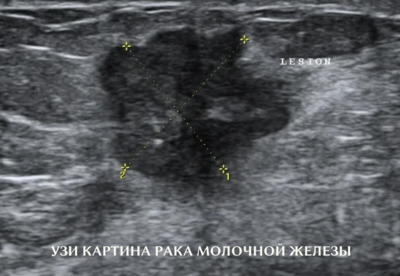

Ультразвуковое исследование (УЗИ)

УЗИ используется как дополнительный метод после маммографии, особенно у молодых женщин с плотной тканью груди, когда рентгеновские лучи менее информативны. Метод эффективен для оценки плотности и размера новообразований, их отношения к окружающим тканям.